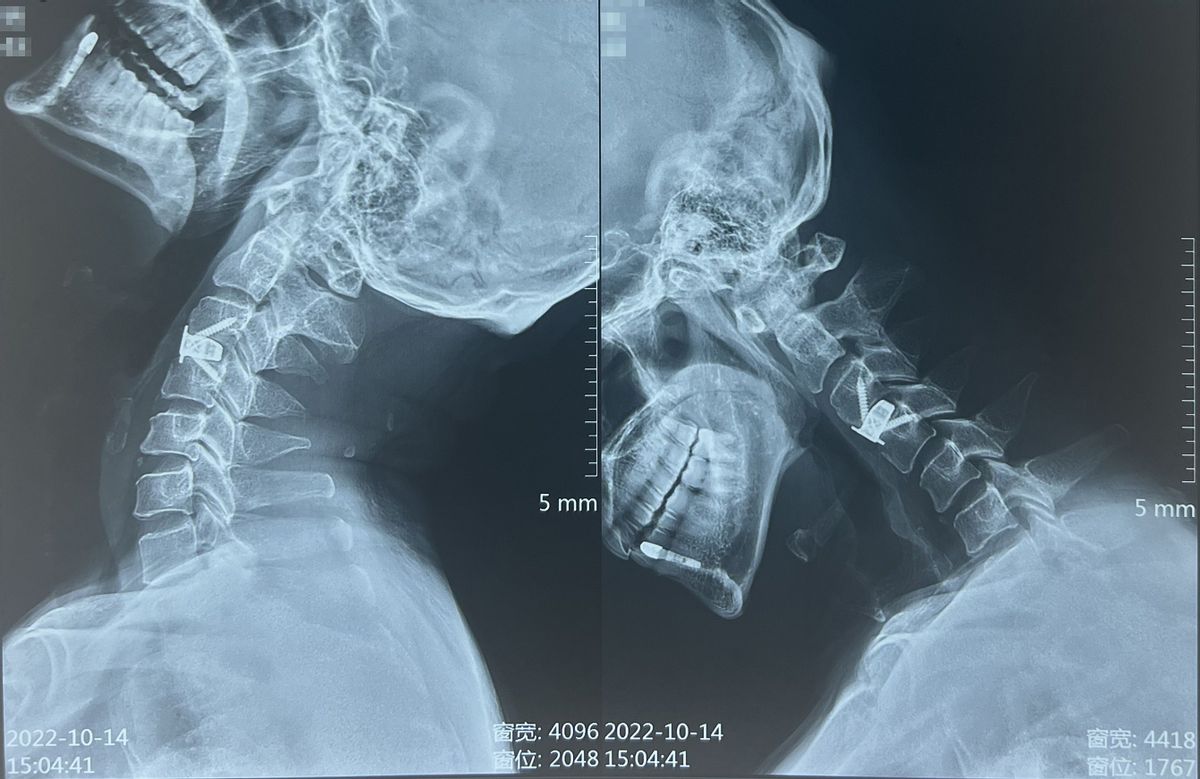

那到底是什么问题导致刘先生出现这些严重症状呢?经过核磁共振等影像学检查后,我们发现刘先生的颈3/4椎间盘出现了突出,并且已经严重压迫到脊髓,建议他尽快考虑手术减压。

针对于刘先生的这些顾虑,再紧密结合他具体的病情,最终我们为他制定了单节段的颈椎前路间盘切除减压融合术,并决定进行Langer's lines横切口,做一个美容缝合。这种手术在显微镜下进行,从颈椎前方入路利用自然解剖间隙达到突出椎间盘的节段,进行脊髓减压操作,安全有效。术中对患者的脊髓、神经、肌肉、血管等创伤很小,术后患者恢复快、住院时间段。

我们为刘先生尽快安排了手术。因为他是颈3/4的椎间盘突出,节段较高,进行高位颈椎横切口,还是稍费了些功夫,但是好处是手术微创,术后切口美观。术中给受压脊髓进行了精准、彻底地减压后,成功地进行了固定融合,将3D打印融合器与终板完美贴合,手术圆满完成。